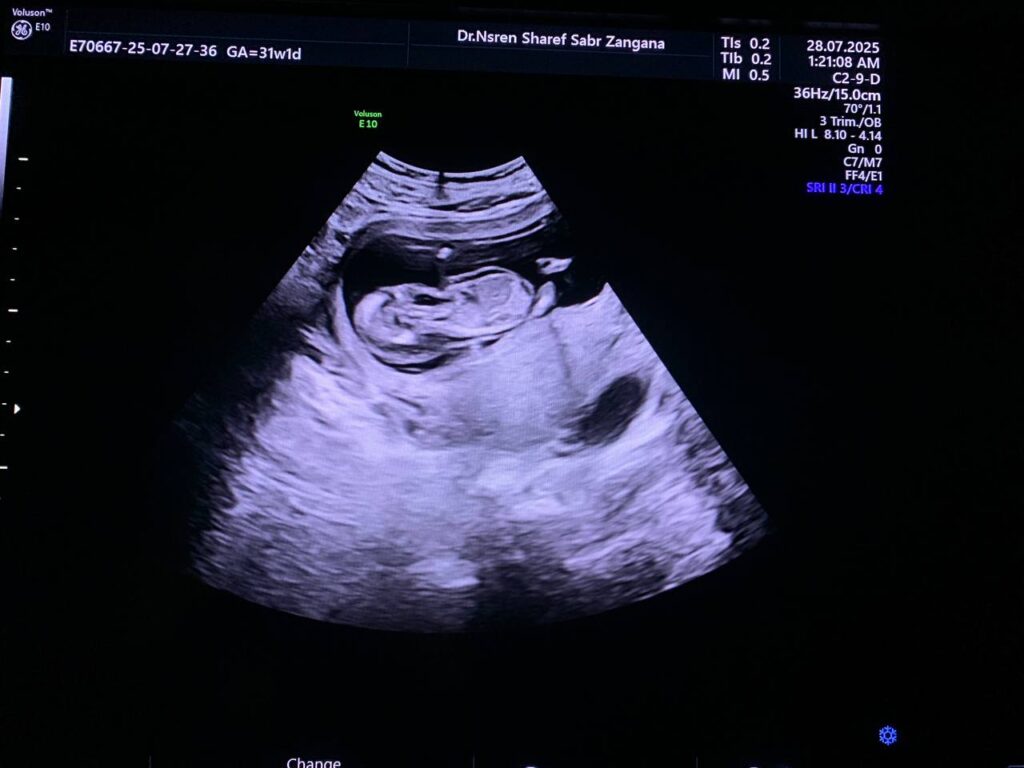

Diffuse edema with Increase nuchal translucency 6.7mm , hypoplastic nasal bone , picture mostly of hydrops fetalis with chromosomal anomaly , please for further study

CRL= 12w+6d